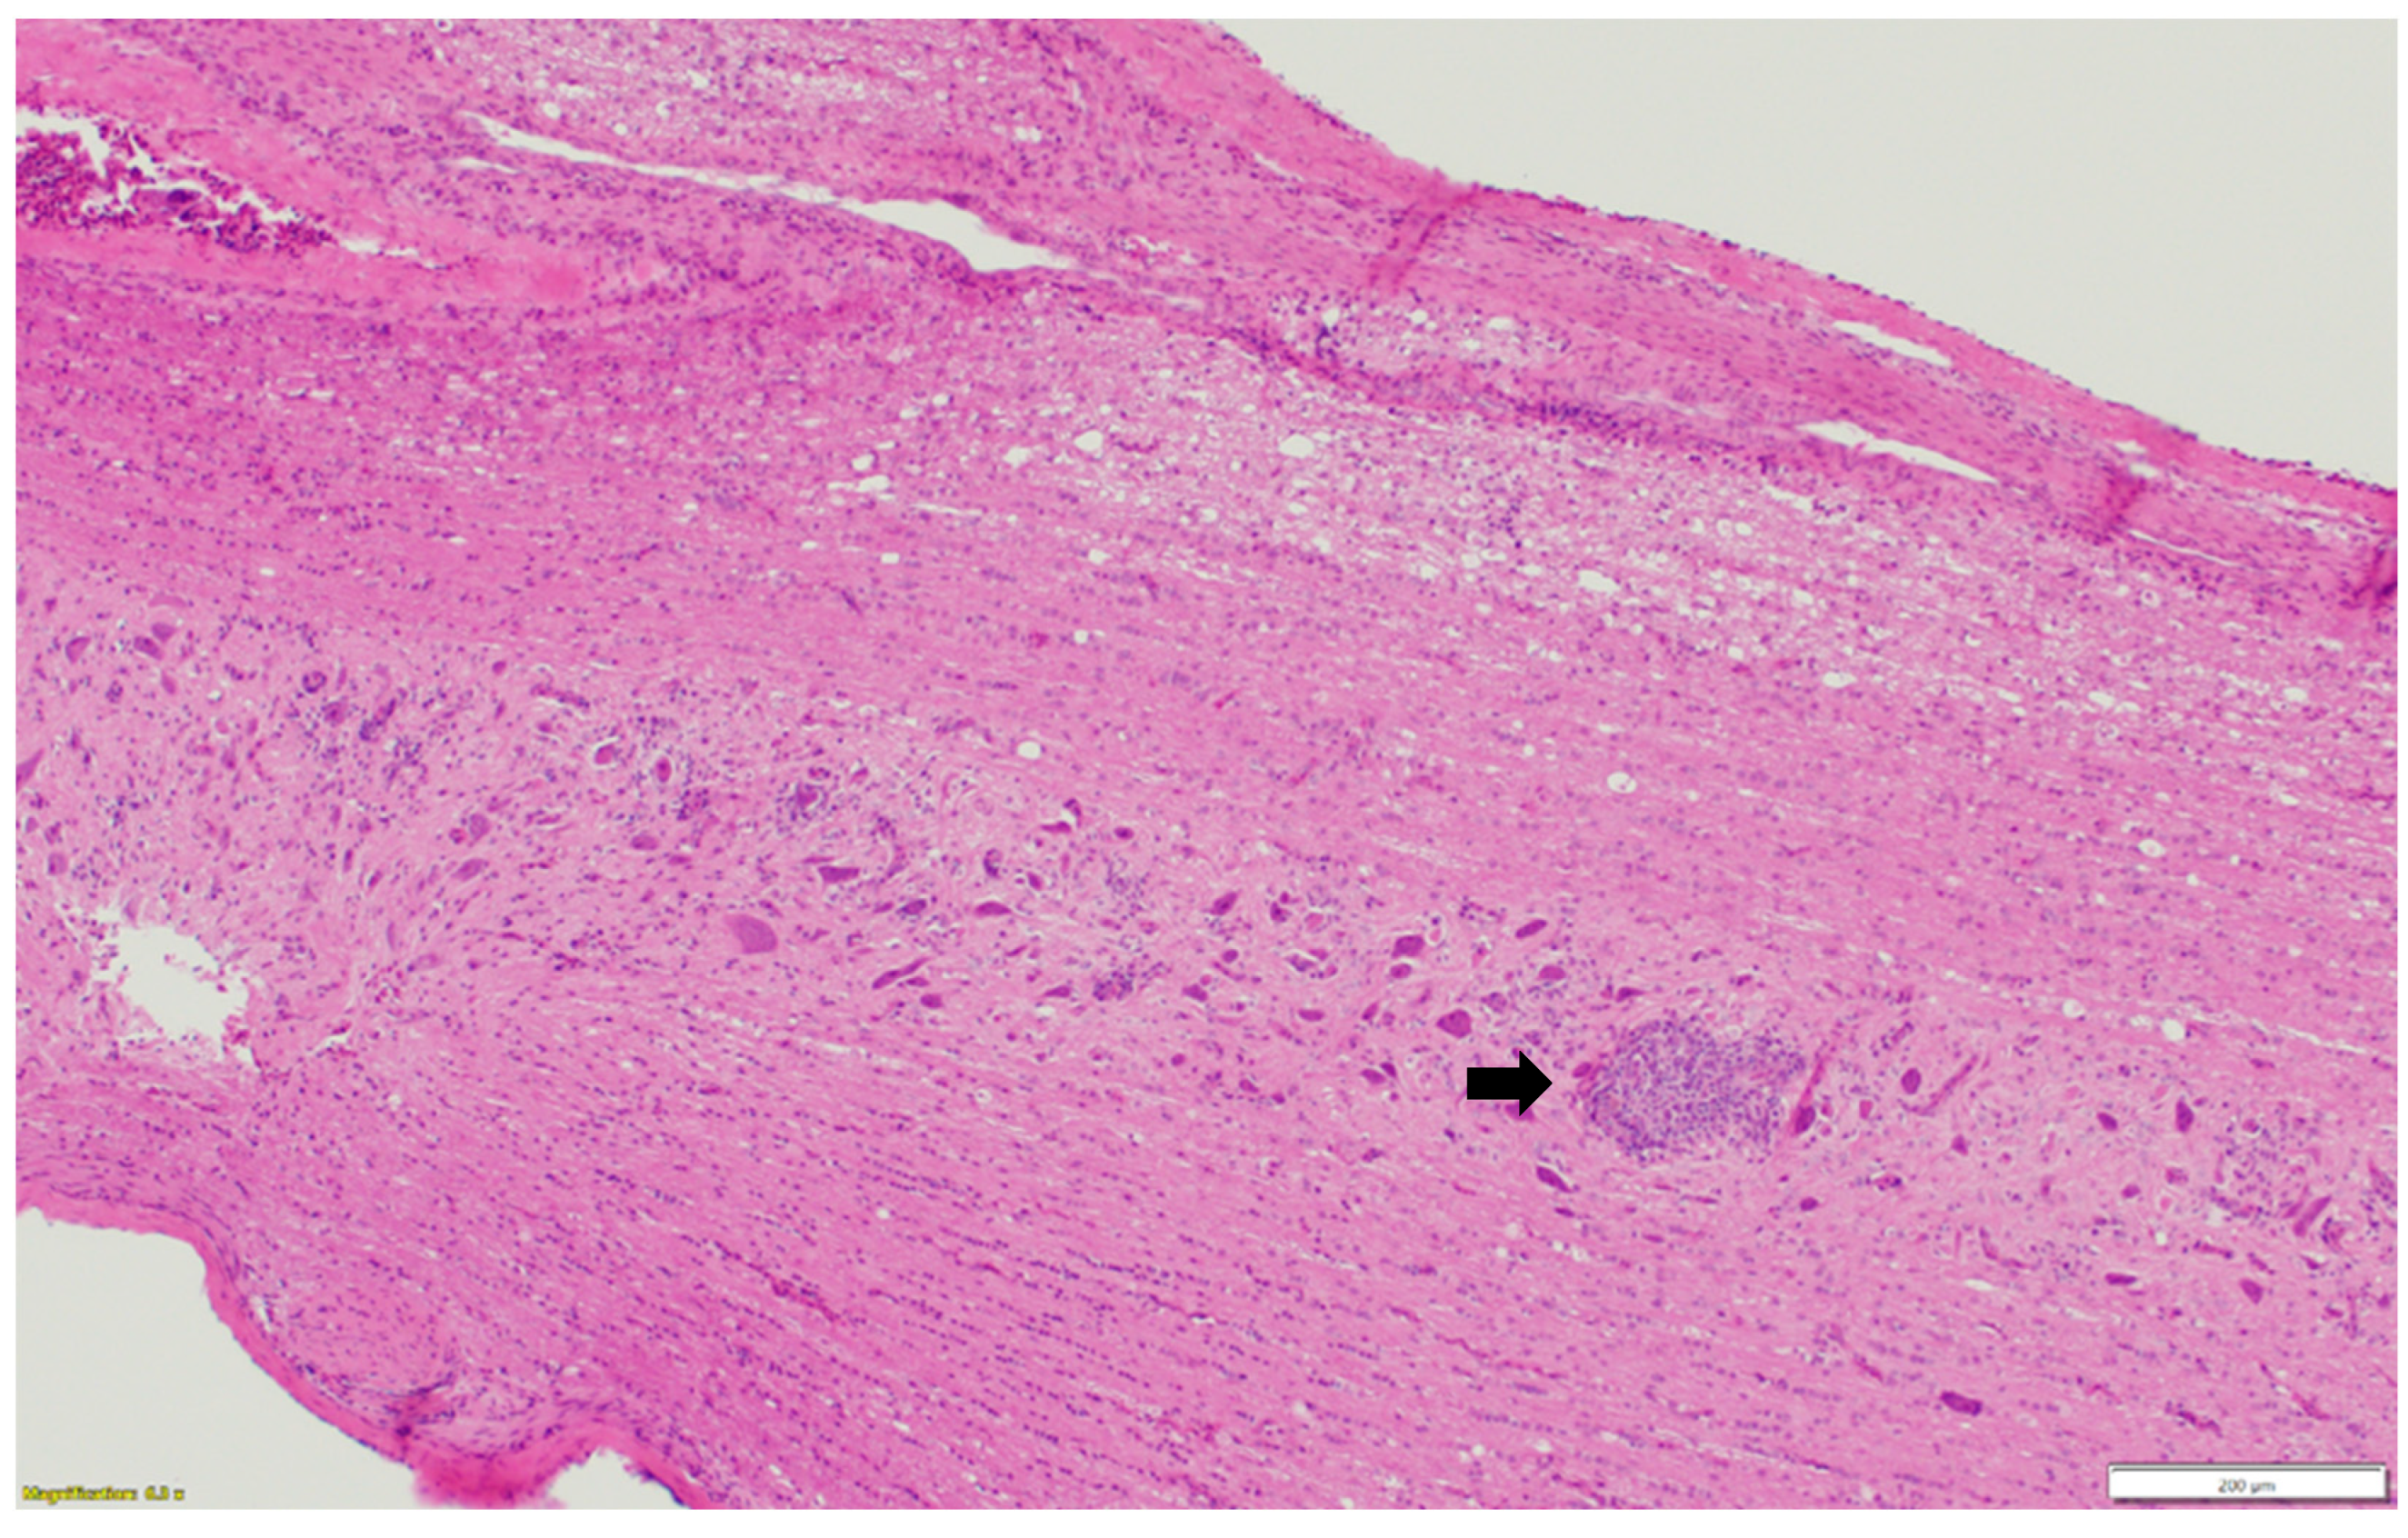

Microscopic examination of different brain, spinal cord, peripheral nerves, and ganglions sections revealed multifocal areas of lymphoplasmacytic and histiocytic infiltrates, indicating encephalitis (Figure 1) in the cerebral white matter, thalamus, hippocampus, and medulla oblongata close the ventricular space. The inflammatory cells around the vessels (perivascular cuffing) as well as around the neurons (satellitosis and neuronophagia) resulted in several neuronal degeneration and central chromatolysis (Figure 2). The gray matter in the spinal cord had multifocal lymphoplasmacytic infiltrates, indicating myelitis (Figure 3). In addition, there was mild to moderate multifocal ganglioneuritis in the pelvis ganglions (Figure 4).

Figure 3. Multifocal lymphoplasmacytic infiltration (black arrow) in the gray matter of spinal cord. Paraffin-embedded tissue was stained with hematoxylin and eosin.